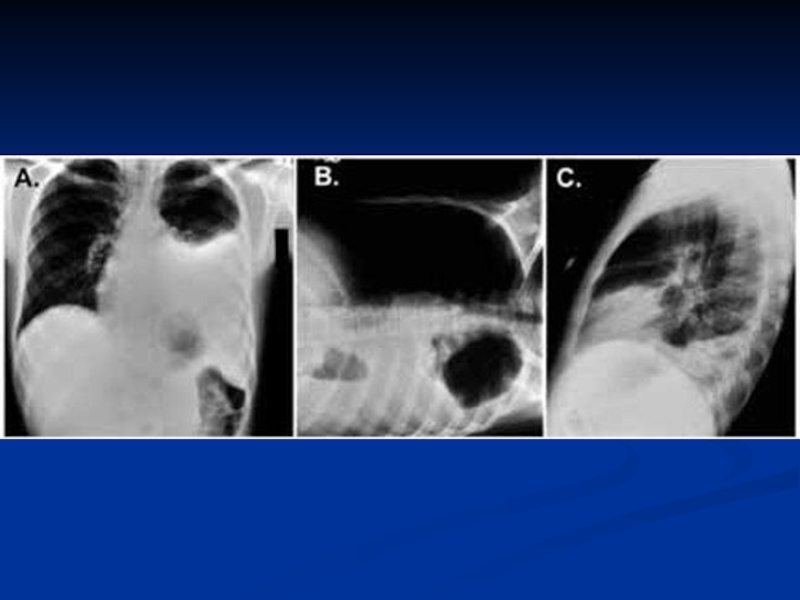

Слайд 18Легочно-гнойным процессом

деструкция

абсцесс

плеврит

пневмоторакс

Легочно-гнойным процессомдеструкцияабсцессплевритпневмоторакс